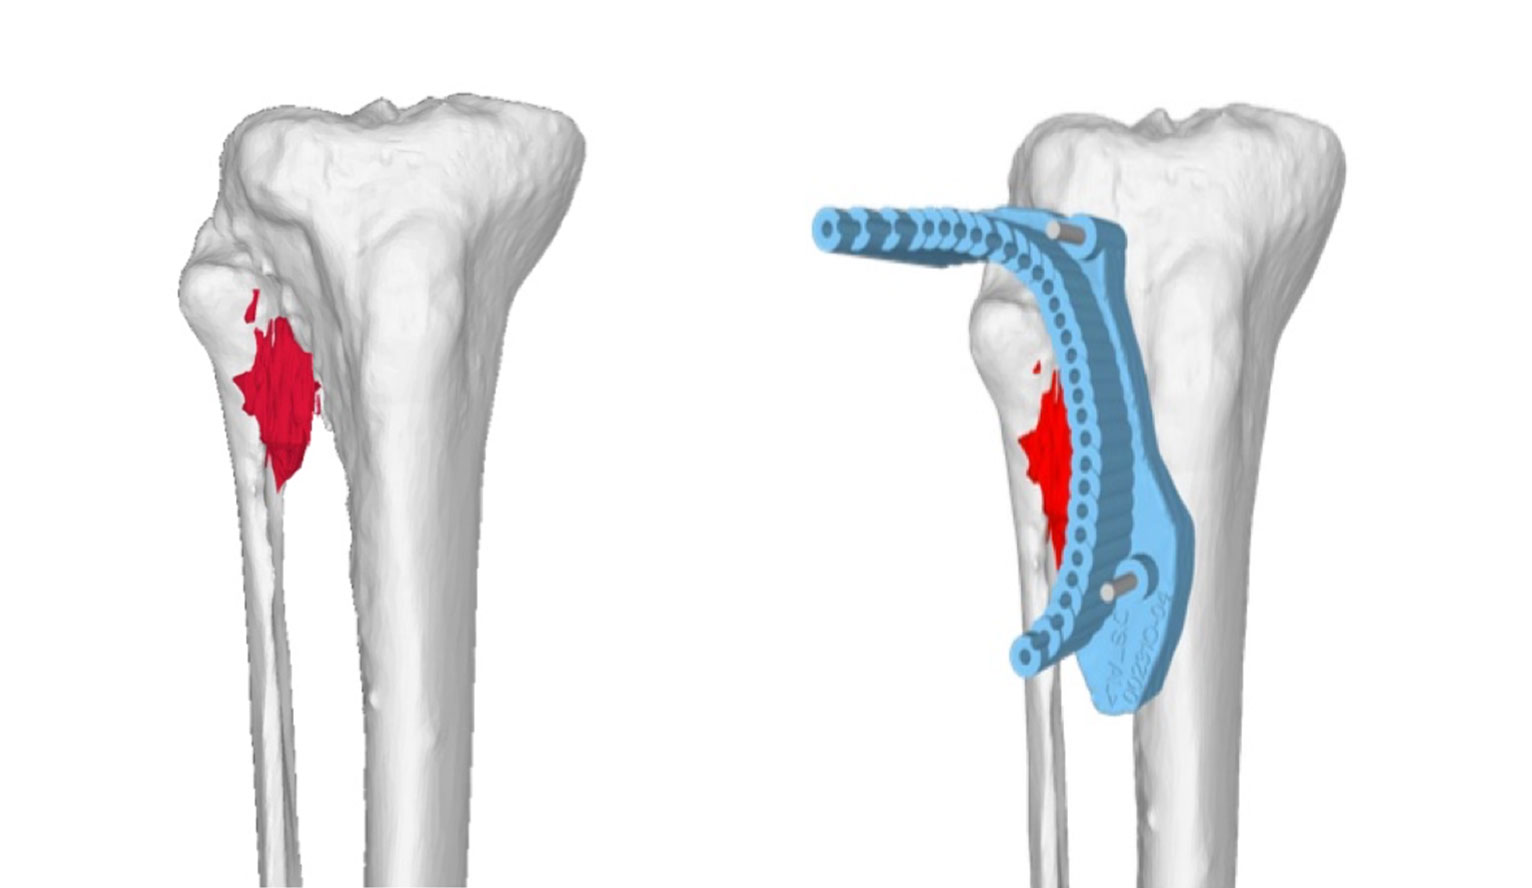

Planung der Tumorentfernung

Als einzige Klinik der Schweiz kann der Balgrist ein 3D-Modell des Tumors erstellen und die Entfernung millimetergenau am Computer planen. Während der Operation kommen spezifisch hergestellte Schnittblöcke aus dem 3D-Drucker zur Anwendung, damit die Planung exakt umgesetzt werden kann. Vor der Operation besprechen wir in einem persönlichen Gespräch mit dem Patienten die einzelnen Schritte der Operation und klären offene Fragen.